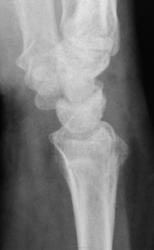

Боли. Травма в анамнезе была, но за помощью не обращался.

Похоже вколоченный перелом диафиза лучевой кости.

Перелом метаэпифиза луча

консолидированный вколоченный перелом метаэпифиза лучевой кости